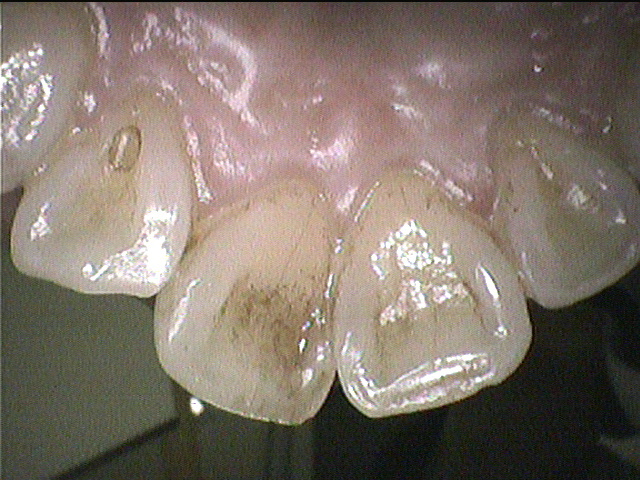

後

クリーニング前

上下の前歯の裏側はステインの付着がありましたので、

できる範囲で除去しました。